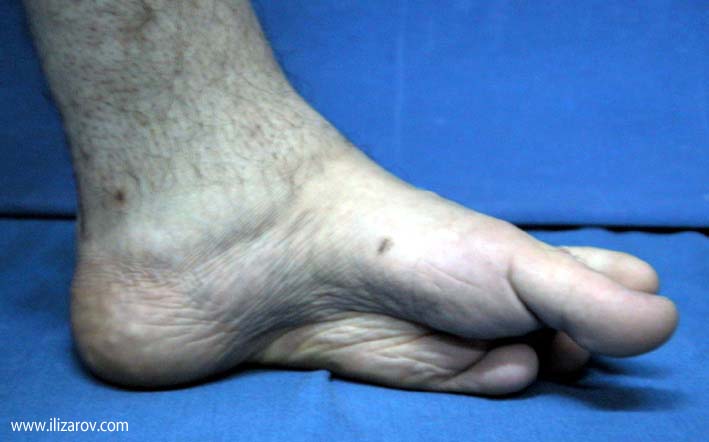

Complex foot deformities can ocur after trauma, neglected or relapsed clubfoot, poliomyelitis, osteomyelitis, burn contracture, neuromuscular diseaes and similar disorders. When treating this deformity with wide soft tissue releases, osteotomies and arthrodesis, there are disadvantages such as the risk of neurovascular injury, soft tissue problems and shortening of the foot. Besides, treating previously operated cases is even harder.

The aim of treatment in foot deformities is to acquire painless and fuctional foot which is plantigrade and at normal size. With the Ilizarov method, correction is planned in 3 planes and performed at a rate depending on the type and degree of the deformity. The deformity is corrected without shortening of the foot, with minimal surgical morbidity and the rate and direction of correction is controlled by the surgeon.